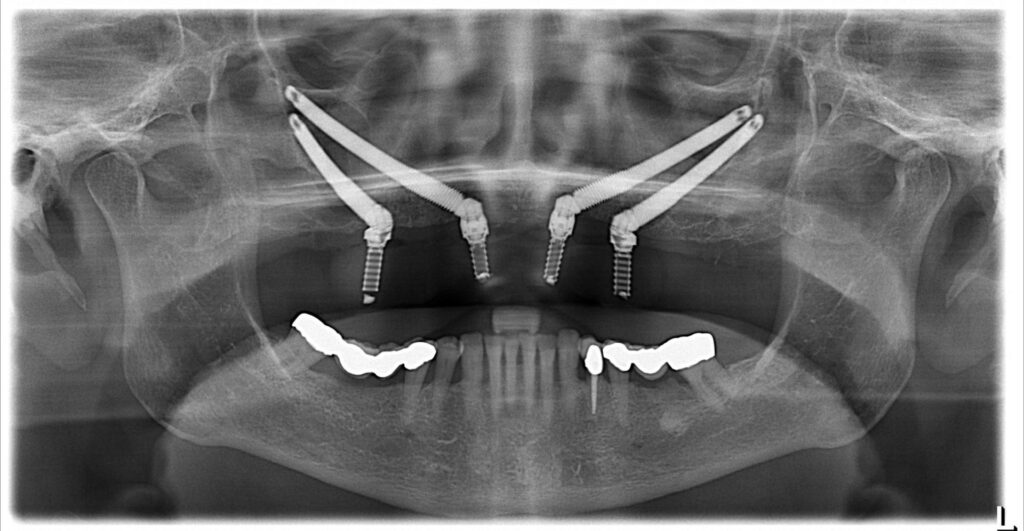

Implantologie dentaire : comment l’imagerie et la planification 3D redéfinissent les implants dentaires à Montréal

Les implants dentaires vivent une véritable révolution. Grâce à l’imagerie 3D et à la planification numérique, les traitements sont désormais plus précis, confortables et prévisibles. Découvrez comment ces technologies transforment l’implantologie à Montréal et ce qu’elles signifient pour votre sourire.